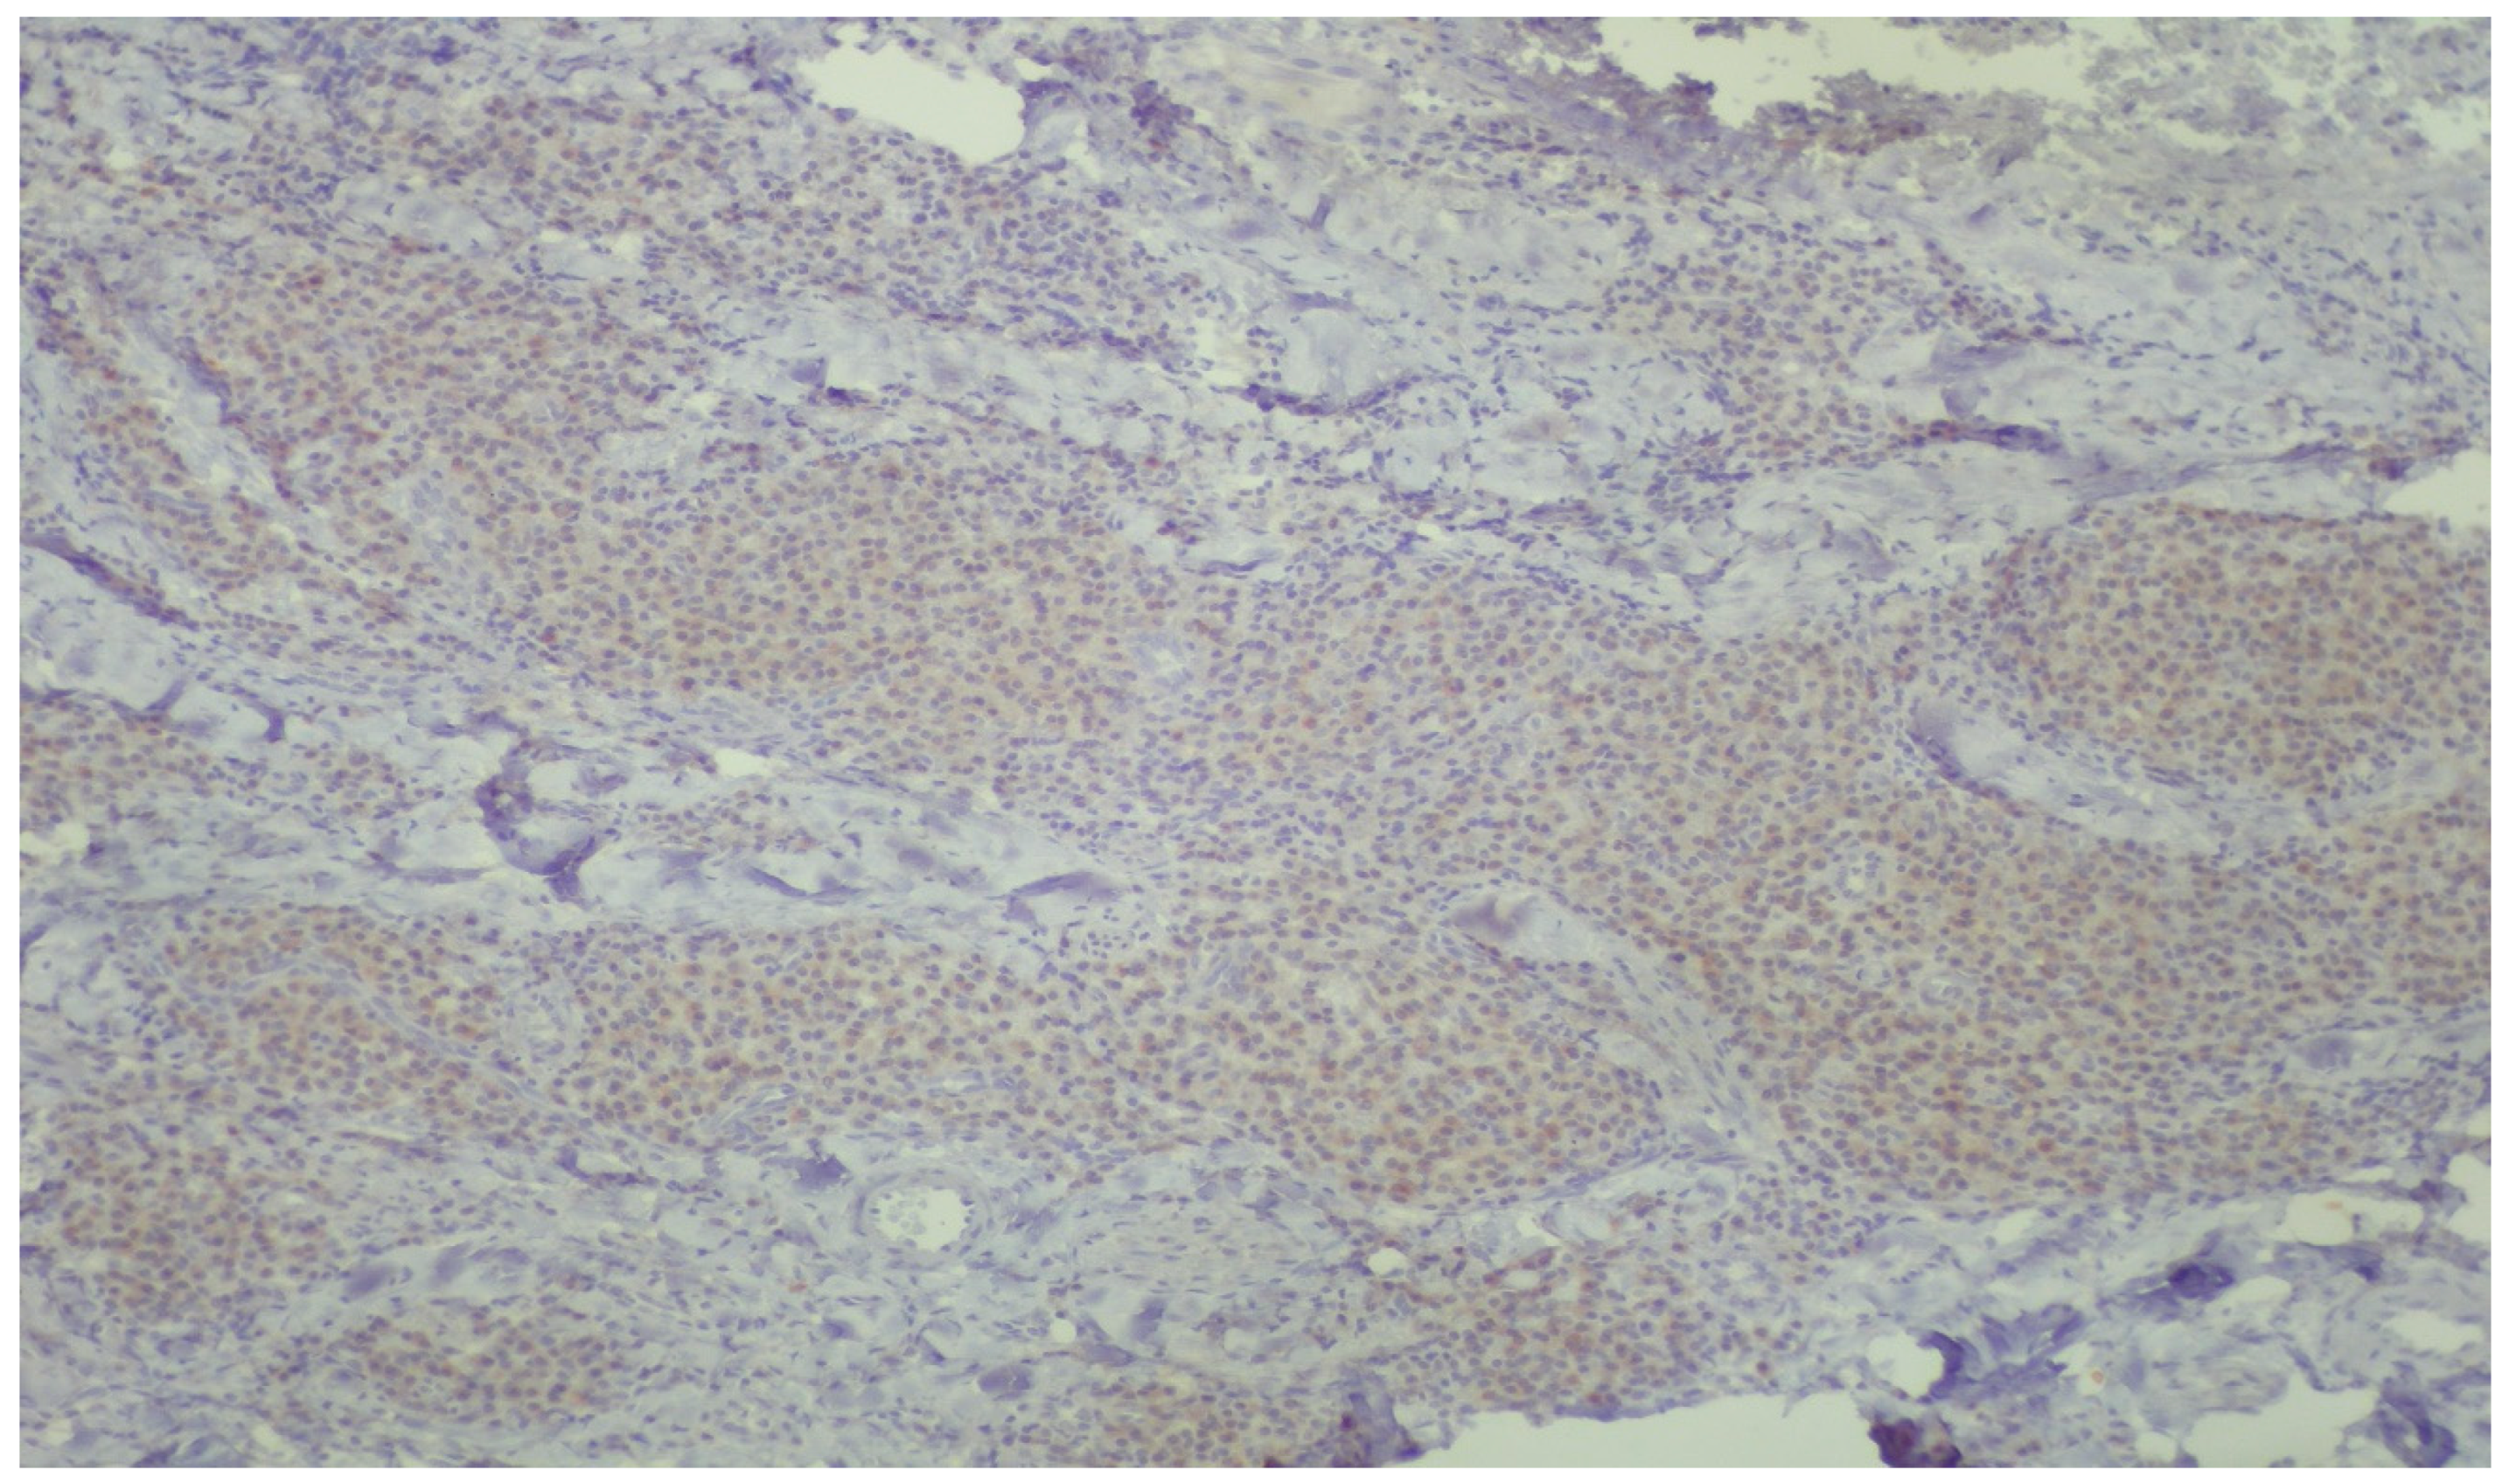

| Parameter | Patient Group | Sample Count | Mean ± SD | p-Value |

| % of Positive Inflammatory Cells | Periodontal Disease and Diabetes (Test) | 13 | 49.2 ± 35.97 | 0.036 |

| Periodontal Disease Only (Control) | 9 | 19.7 ± 34.40 | ||

| Allred Score (% Positive Cells × Intensity) | Periodontal Disease and Diabetes (Test) | 13 | 59.6 ± 49.52 | 0.036 |

| Periodontal Disease Only (Control) | 9 | 20.8 ± 34.21 | ||

| Staining Intensity | Periodontal Disease and Diabetes (Test Group) | Periodontal Disease Only (Control Group) | p-Value |

|---|---|---|---|

| Negative (0) | 2 (15.4%) | 5 (55.6%) | |

| Mild (1) | 9 (69.2%) | 3 (33.3%) | |

| Moderate (2) | 2 (15.4%) | 1 (11.1%) | |

| Chi-square test | 0.174 |